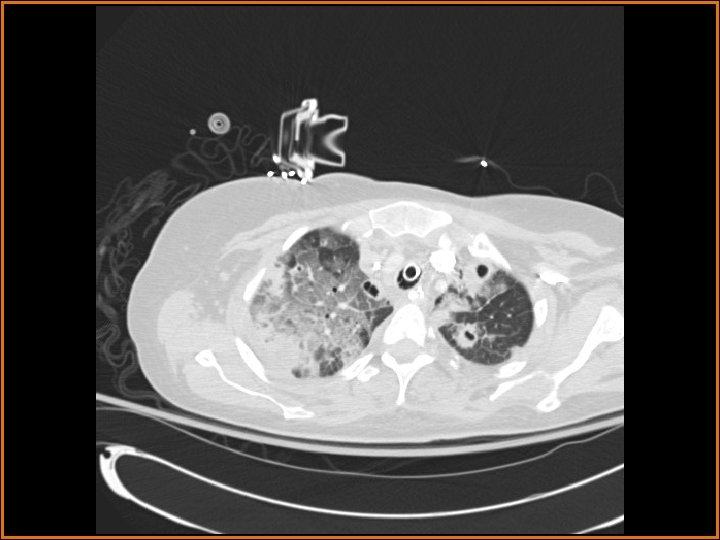

Findings and Differentials CT Findings: Multiple bilateral peripheral nodular opacities are seen, many of which are fed by arterial branches. Some of the nodules are cavitary. Diffuse bilateral ground glass opacities are seen with air bronchograms. The large lucency projecting over the right hemidiaphragm on the plain film corresponds to a pleural air collection that is directly contiguous with one of the cavities. Differential Diagnosis: • Multiple cavitary metastases • Septic Emboli

Discussion The differential diagnosis of cavitary nodules includes cavitary metastases, septic emboli, fungal infections, rheumatoid nodules, Wegener's granulomatosis, and rheumatoid nodules, among others. In this patient with fever, an infectious or inflammatory etiology is at the top of the differential. Correlation of the history with the imaging findings supports the diagnosis of septic emboli. Septic emboli usually manifest as multiple, bilateral peripheral opacities which may or may not cavitate. Often, the emboli will be in different stages of cavitation. Demonstration of a feeding vessel into the nodules indicates the hematogenous etiology of this process (although hematogenous metastases and a small-vessel vasculitis could certainly exhibit this feature also). Septic emboli may lead to pulmonary infarctions, which are seen as wedge-shaped opacities abutting the pleural surface, with the apex of the triangle pointing away from the pleura. The periphery of the infarct can enhance, but the center usually does not. Distinguishing infarcts from pneumonia is made easier when a vessel can be seen terminating at the apex of the infarcted region. (CONTINUED ON NEXT SLIDE)

Discussion (Continued) In this patient, the large right anteroinferior pleural air collection is contiguous with one of the cavities (as seen on the second CT image) and represents a bronchopleural fistula. Etiologies of bronchopleural fistulas include necrotizing infection, active TB, irradiation, tumor in a bronchial margin, etc. If the bronchopleural fistula is large, a persistent pneumothorax with or without contralateral mediastinal shift may be present. In this case, a septic embolus had eroded into the pleural space, creating the lucent collection projecting over the right hemithorax on the plain films. Finally, the ground glass opacities represented pneumonia in this patient.